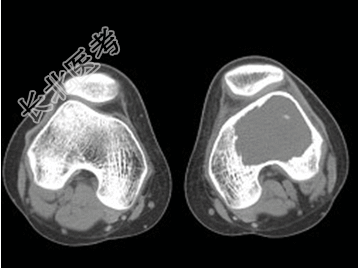

- [材料题] 患者,男,33岁,左股骨肿块半年余,无明显症状,查体一般情况良好。

- 简答题1、结合所提供的图像,该患者诊断为?